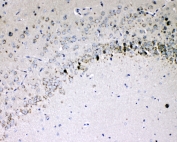

IHC staining of FFPE rat brain with Il-16 antibody at 1ug/ml. HIER: boil tissue sections in pH6, 10mM citrate buffer, for 10-20 min followed by cooling at RT for 20 min.